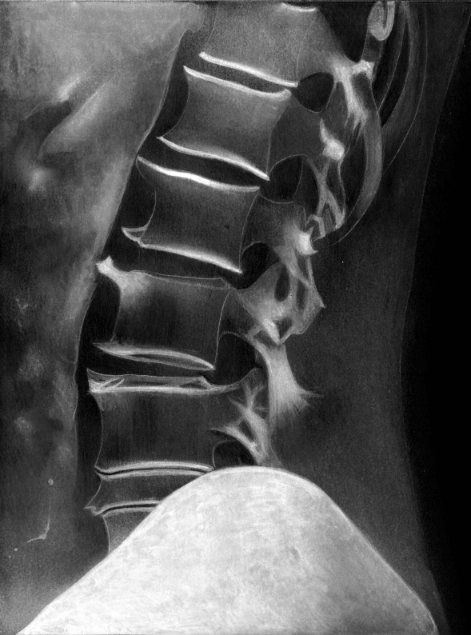

Dolor de columna por artrosis:

Mantener un peso adecuado, La obesidad es una causa de la enfermedad y la hace progresar más rápidamente.

Aplicar calor o frío. El calor aplicado sobre el área afectada alivia el dolor y relaja los músculos. Cuando la zona afectada con artrosis presenta un brote inflamatorio, es útil la aplicación de frío.

Cumplir con el plan analgésico indicado por el médico.

Mantener hábitos posturales tales como dormir en una cama plana, evitar sentarse en sillones hundidos, y emplear sillas con respaldo recto, manteniendo las caderas y las rodillas en su posición natural y apoyando los pies en el suelo.

Realizar ejercicios tales como caminar, andar en bicicleta o nadar. Evitar deportes de contacto físico o carga física.

Mantenerse en reposo durante los periodos de dolor intenso.

No sobrecargar las articulaciones con peso.

Utilizar calzado adecuado.